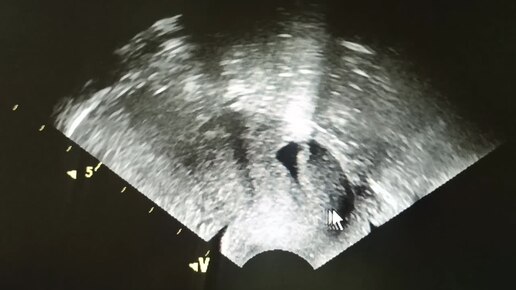

Начинающим врачам УЗИ: ниша в области рубца от кесарева сечения